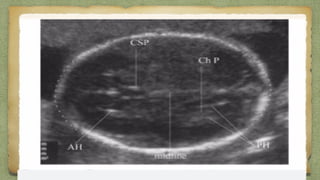

๏ฑ Correct levels

๏ฑ Measured at a focus which shows, both the THALAMITHALAMI &

the CAVUM SEPTUM PELLUCIDUMCAVUM SEPTUM PELLUCIDUM..

CSPCSPThalamusThalamus

Lateral LobeLateral Lobe

VermisVermis

CisternaCisterna

MagnaMagna

Choroid PlexusChoroid Plexus

MeasurementMeasurement

The outer table of the skull on the superior end of the image upto theThe outer table of the skull on the superior end of the image upto the

inner table of the skull at the inferior end of the imageinner table of the skull at the inferior end of the image